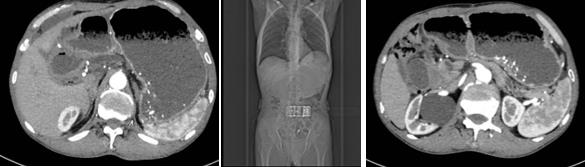

十二指肠梗阻、胃留严重

确定治疗方案后由消化内科鲍峻峻副主任医师、洪江龙副主任医师等为患者实施手术,通过超声内镜精准定位,于胃底处扫查可见邻近扩张肠管。超声电切引流支架在超声内镜引导下避开大血管及重要脏器,直接穿刺入扩张肠管内,释放双蘑菇头金属支架,超声内镜下胃-空肠吻合术的顺利完成,手术全程无明显出血。